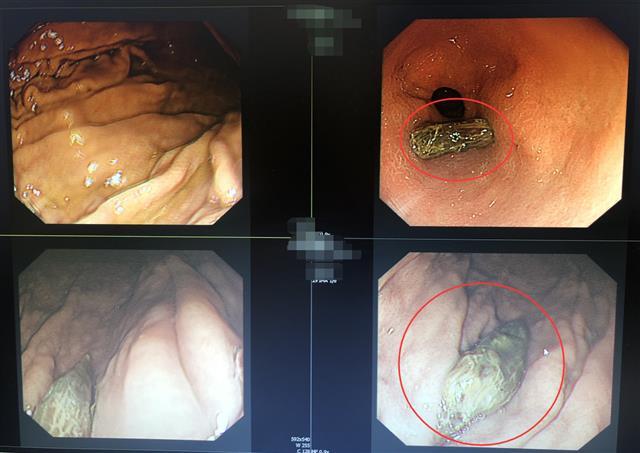

在胃镜下,江军发现陈爹爹胃壁内“横卧”着一颗大枣核,它的两端稳固地“扎根”于粘膜内,触之不动,“上不来”也“下不去”。他使用异物钳、取异物网兜等器械,将陈爹爹胃壁中的大枣核顺利取出,未出现大出血、穿孔等并发症。术后,陈爹爹上腹部疼痛随即消失。